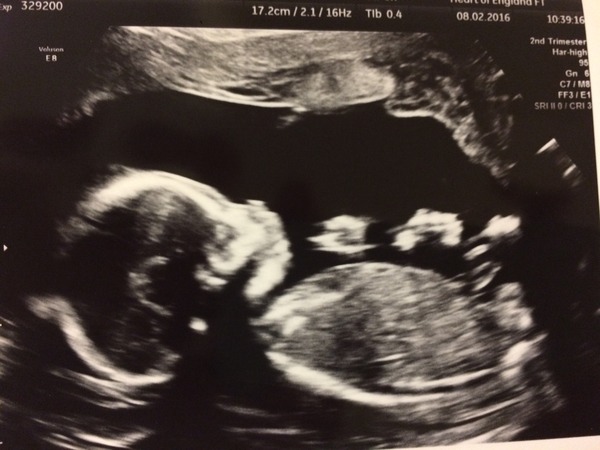

18+2

Team Pink 👶🏼💗

Congrats to everyone that found out what they are having today!! 💗💙

Scan went well, little one wouldn't keep still lol

Also because I have fibroids they want to scan me two more times so I get one at 28 weeks and one at 37 xx

20 week scan today at 10:15, although I am only 19+1. Despite having seen little one 4 times now I am extremely nervous and haven't slept a wink.